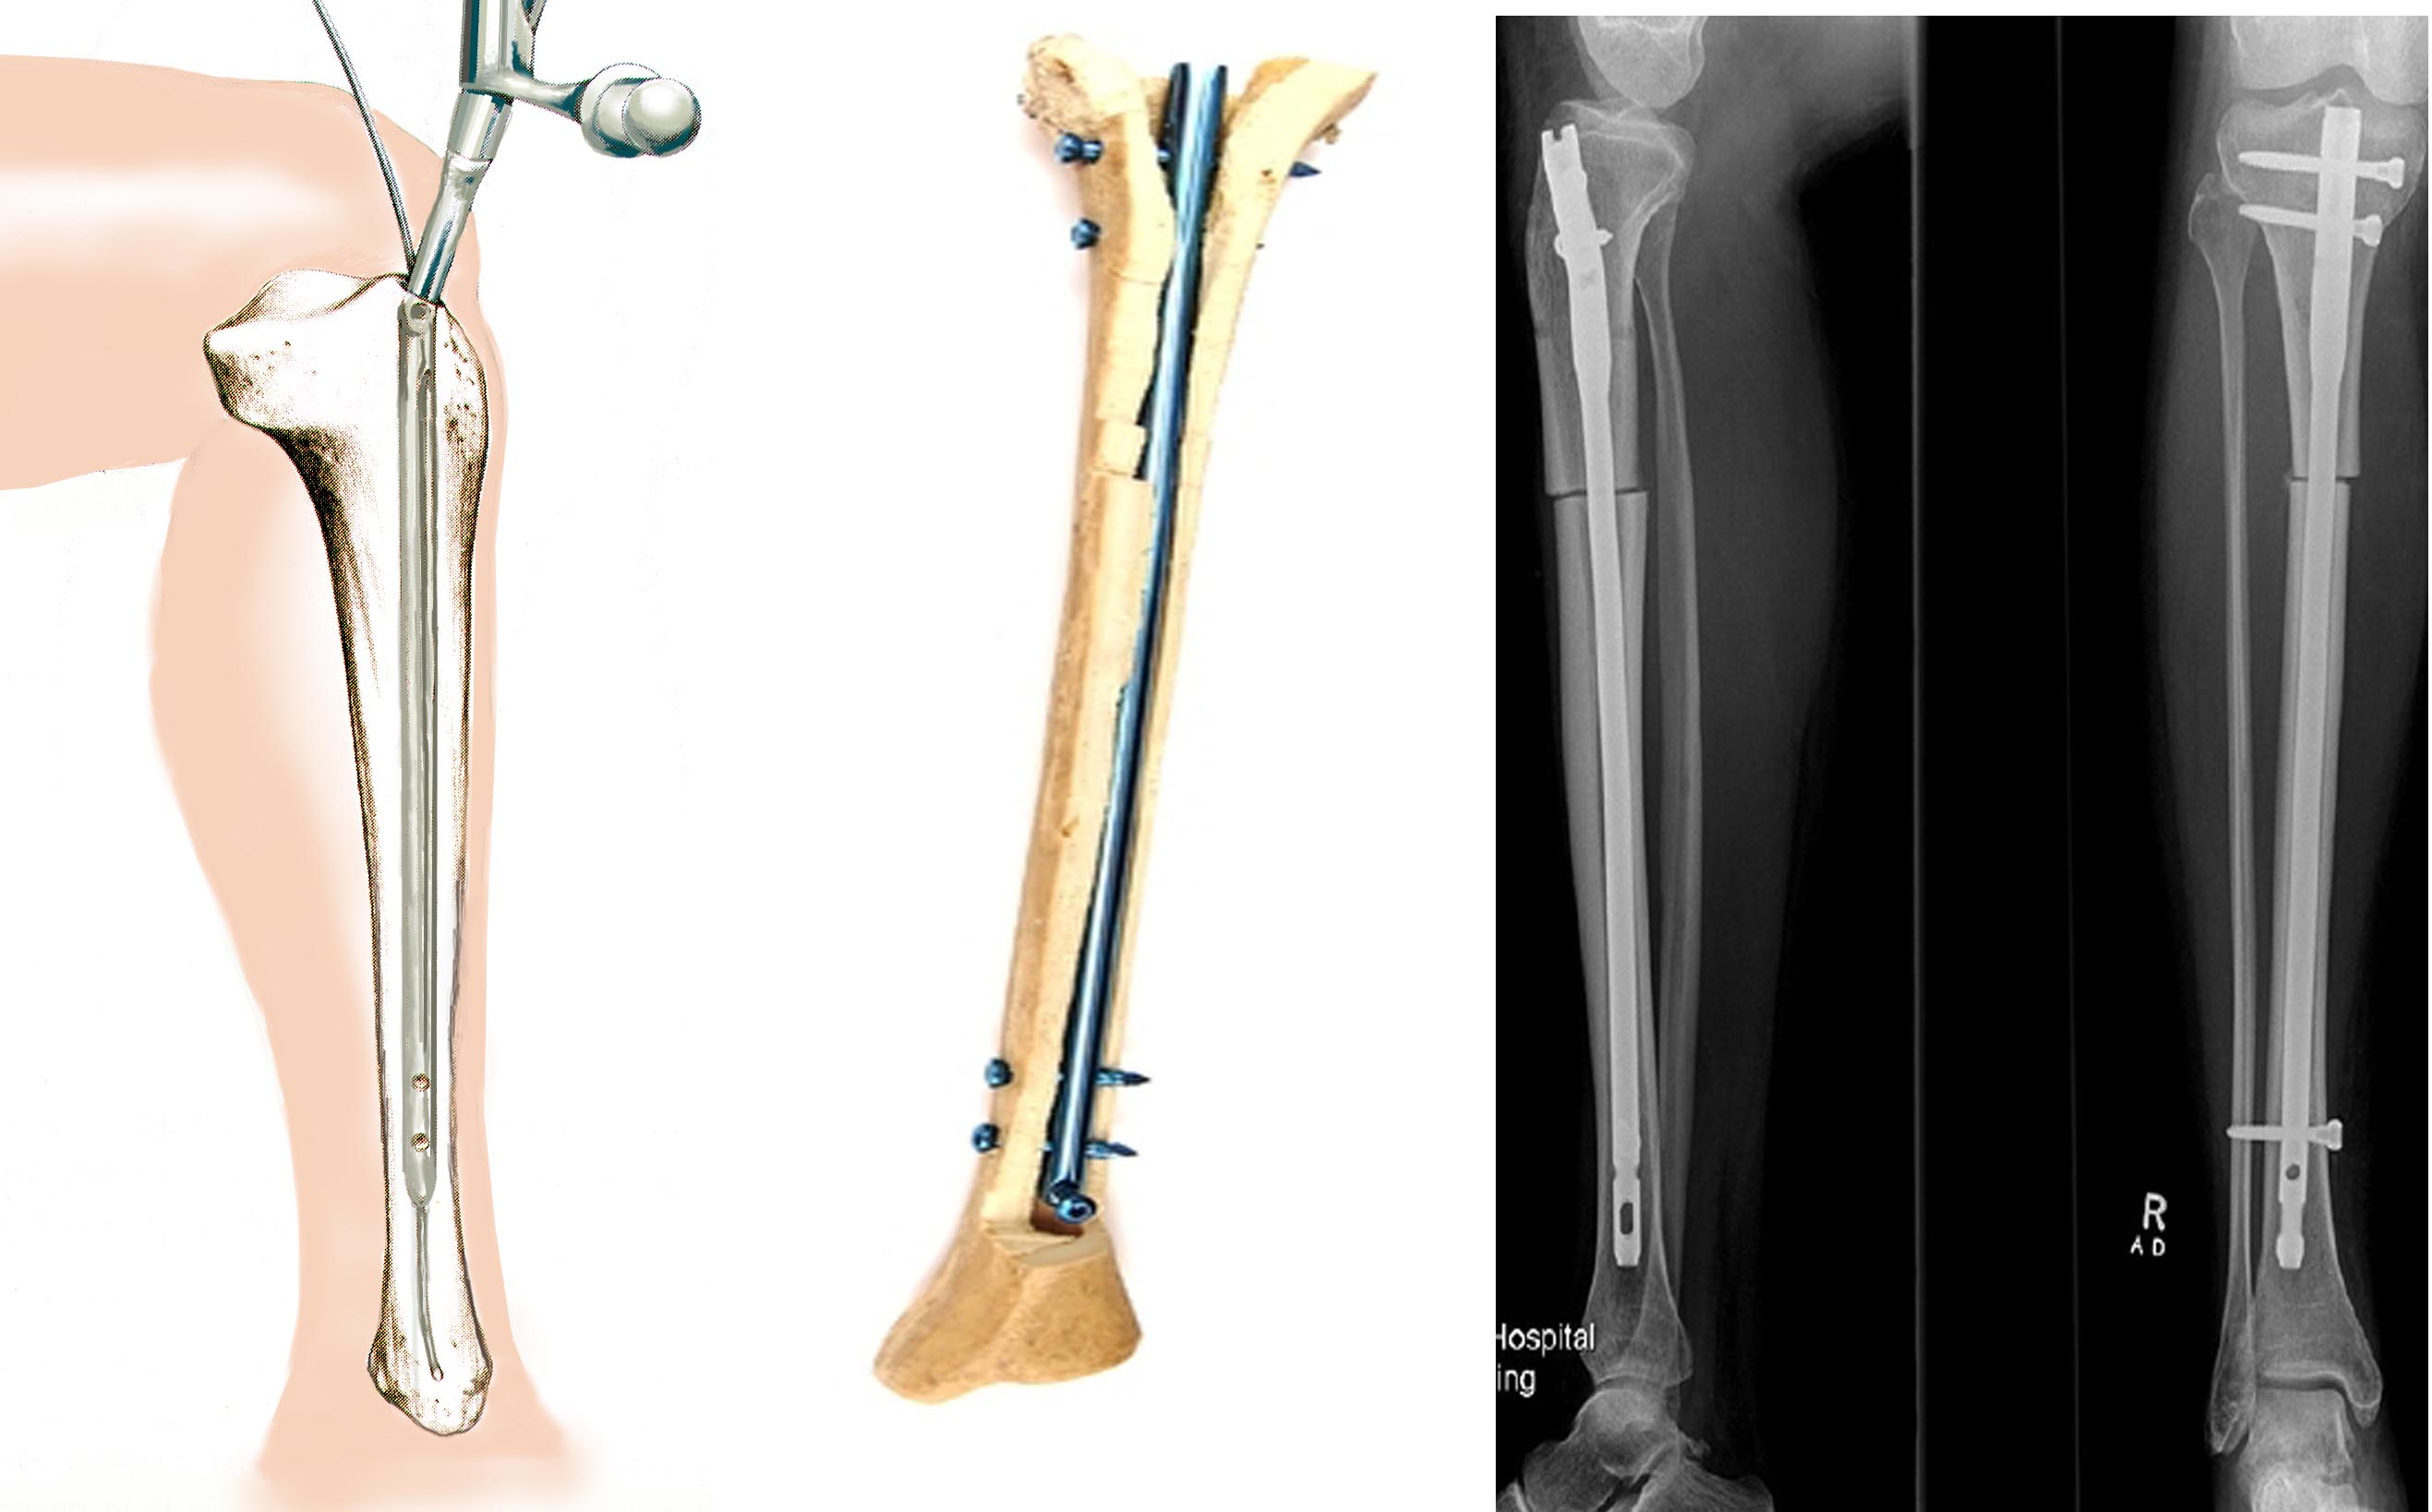

В зависимости от клинической картины, остеосинтез плечевого сустава может быть экстрамедуллярным (с применением пластин) или интрамедуллярным (с использованием спиц). Эти две разновидности операций относятся к группе внутренних, то есть погружных. Для фиксации отломков в этом случае могут использоваться винты, спицы, штифты, пластины, проволока. Внешний (чрескожный) вариант – это установка аппаратов внешней фиксации, самый известный – аппарат Илизарова.

Особенности применения штифтов

При внутрикостном оперативном лечении штифты вводят в костномозговую полость длинных частей трубчатых костей. Преимущества методики – низкая травматичность, возможность уже через несколько дней давать нагрузку на травмированную конечность.

Операция проводится при поперечных переломах костей с достаточным объемом костномозговой полости. Для более прочной фиксации используют штифты с отверстиями для винтов, которые проводят через кость. Это БИОС, то есть блокированный интрамедуллярный остеосинтез. Также используются самоблокирующиеся штифты Fixion. Они позволяют сделать операцию максимально быстро и используются даже при оскольчатых переломах.